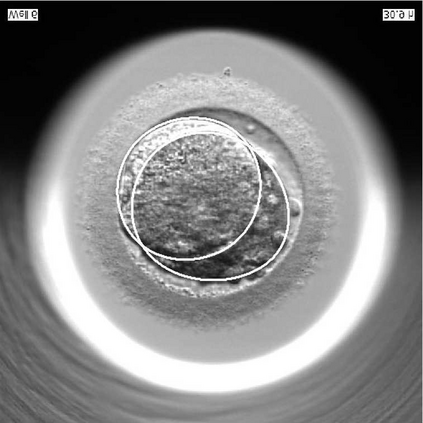

We present a novel method for identification of the boundary of embryonic cells (blastomeres) in Hoffman Modulation Contrast (HMC) microscopic images that are taken between day one to day three. Identification of boundaries of blastomeres is a challenging task, especially in the cases containing four or more cells. This is because these cells are bundled up tightly inside an embryo's membrane and any 2D image projection of such 3D embryo includes cell overlaps, occlusions, and projection ambiguities. Moreover, human embryos include fragmentation, which does not conform to any specific patterns or shape. Here we developed a model-based iterative approach, in which blastomeres are modeled as ellipses that conform to the local image features, such as edges and normals. In an iterative process, each image feature contributes only to one candidate and is removed upon being associated to a model candidate. We have tested the proposed algorithm on an image dataset comprising of 468 human embryos obtained from different sources. An overall Precision, Sensitivity and Overall Quality (OQ) of 92%, 88% and 83% are achieved.